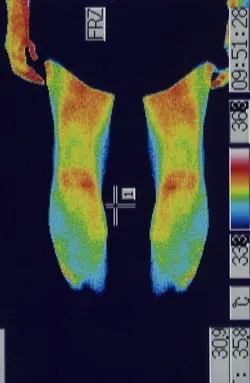

突発性難聴の治療で高圧酸素室に入って治療をした時、耳ぬきがうまくいかずに滲出性中耳炎になってしまいました。痛みは無いので鼓膜に穴をあけるのもとても不安です。滲出性中耳炎は、鍼治療でよくなりますか?

内耳のリンパの流れを良くすることで改善することが多いです。

滲出性中耳炎は、痛みが無いので癖になってしまうことが多いのですが、比較的、鍼治療が効果的です。お医者様は、鼓膜にチューブを入れることがあるのですが、鼓膜の中に落ち込んでしまうこともあるので、鍼治療をされる方も多いです。不安や恐怖が多いほど、症状が改善しなくなることが多いので、ストレスをためないようにしましょう。

詳しくは、 滲出性中耳炎の鍼治療 をご覧ください。